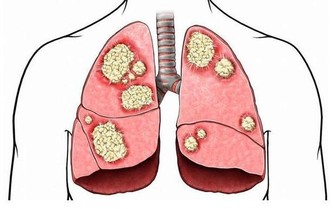

大家要知道,口腔環境是一個有菌環境,有大量微小細菌生活在其中。潔淨的牙齒表面上,會被一層唾液膜覆蓋,然後各種細菌就會在這個膜上“安家落戶”,並且最近繁衍後代,成熟壯大,成為一個又一個的部落,然後形成一個小的細菌社會,這就是醫學上所說的牙菌斑。

牙菌斑可不是什麼“善類”,它裡面的細菌會代謝許多有毒物質,而這些物質就會刺激牙齦組織,誘發炎症。在炎症的狀態下,牙齦就容易充血,較為脆弱,受到機械刺激就容易出血。

牙菌斑在剛剛形成的時候,人可以通過刷牙把它清除乾淨,但如果沒有及時清除乾淨,那麼牙菌斑就會發展變為牙結石,最為糟糕的是牙結石粗糙的表面更容易吸附牙菌斑,這就形成惡性循環,從而加重牙齦的炎症和出血。